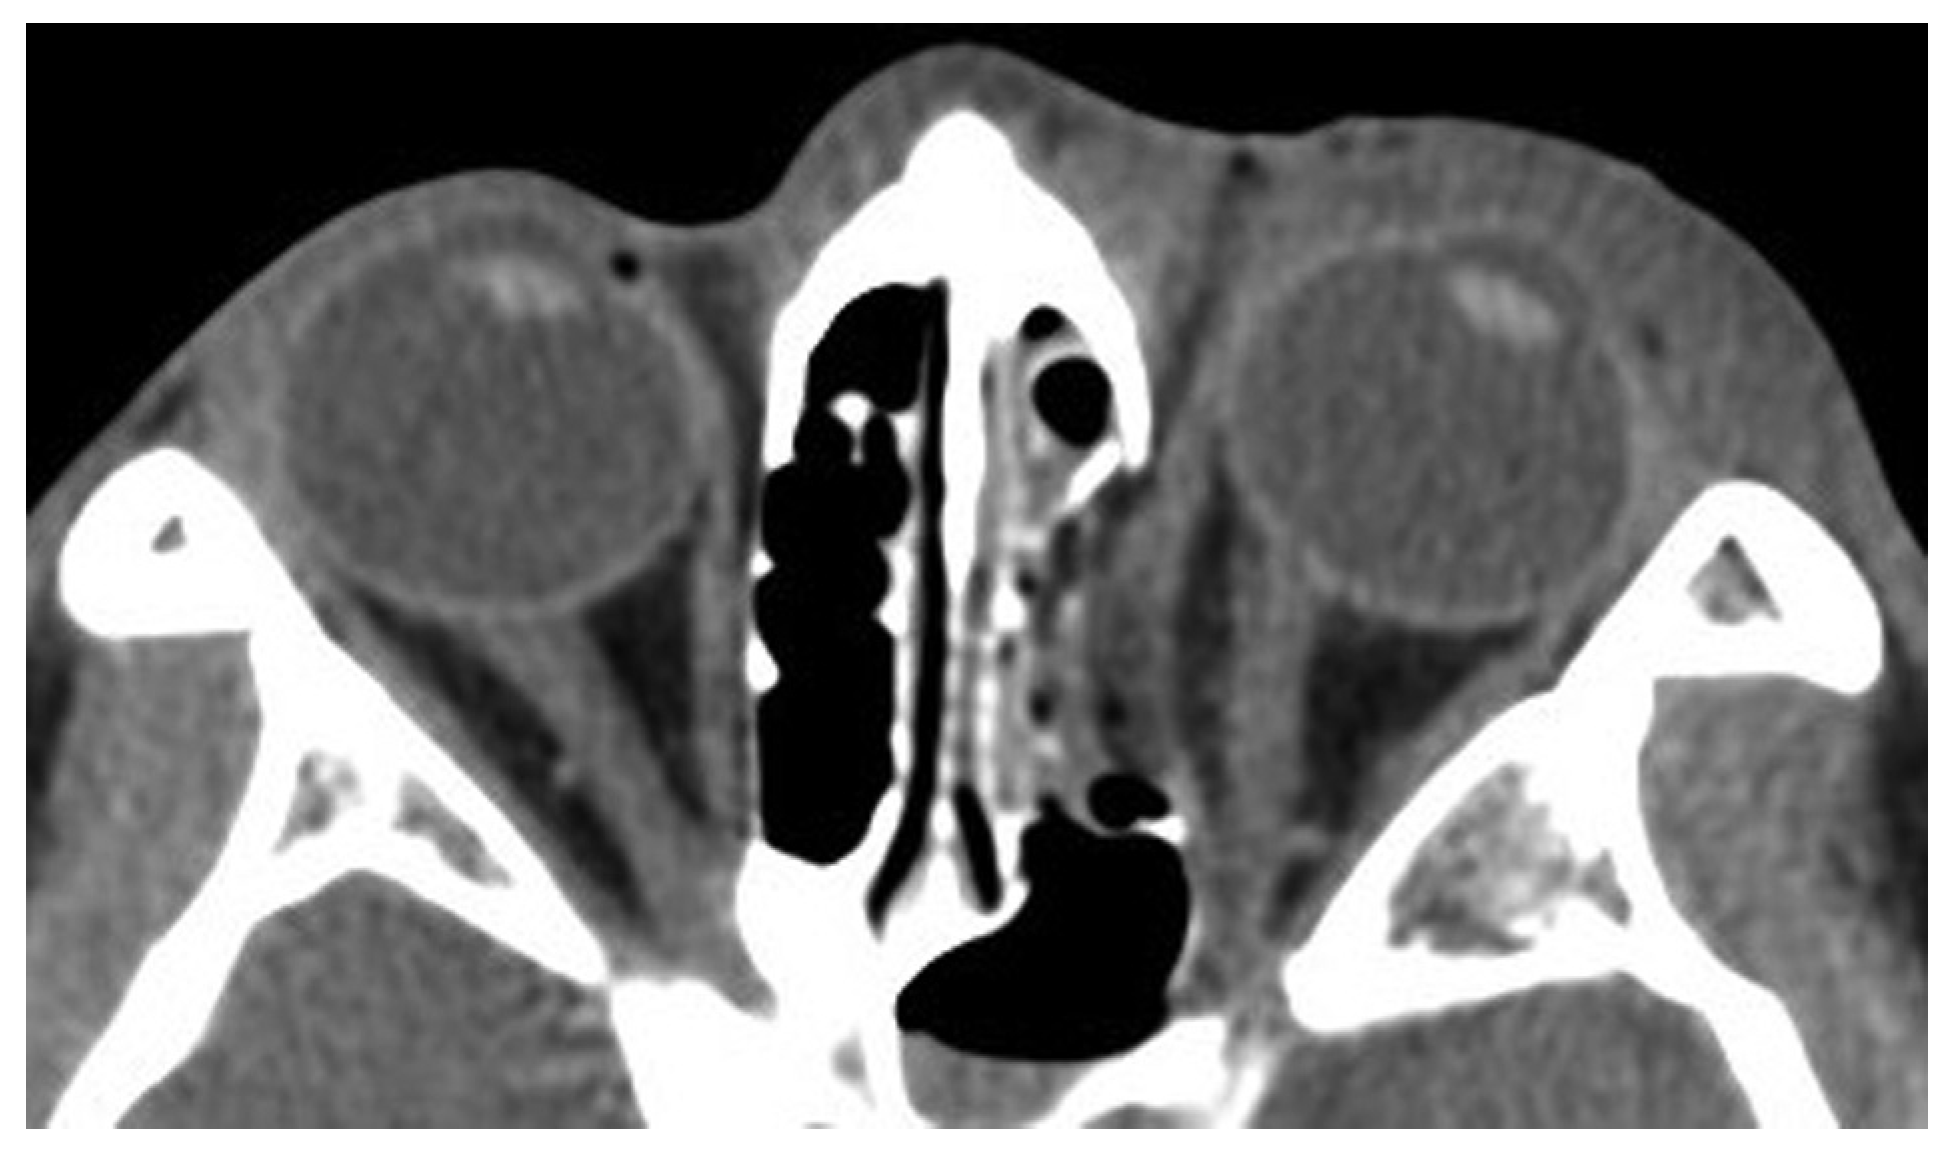

Case 12

A 39-year-old woman sustained facial injuries, and presented with diplopia. She was referred to our clinic by an ophthalmologist for a suspected blowout fracture at 3 weeks after injury. A CT scan revealed bone defect of orbital floor and the displacement of soft tissue into the maxillary (Figure 3). The patient’s left eye movements—up gaze and down gaze—were severely restricted (Figure 4). The diagnosis was a blowout fracture with the orbital floor punched out. Forced duction testing was performed at the beginning of the case to document any preoperative globe restriction. The surgery was performed to reconstruct the orbital floor at 27 days after injury. By transconjunctival approach, the orbital fat and muscle was pulled into the floor cavity, and a 35 mm × 20 mm defect of the orbital floor was seen. A graft was harvested from the sixth right-side rib by splitting it in situ at the size of 50 mm × 15 mm. The split bone was cut and remade into a double leaf using absorbable suture, and gently inserted into the orbital floor without fixation.

Figure 3. Coronal view of CT before surgery. Entrapment of inferior rectus muscle.